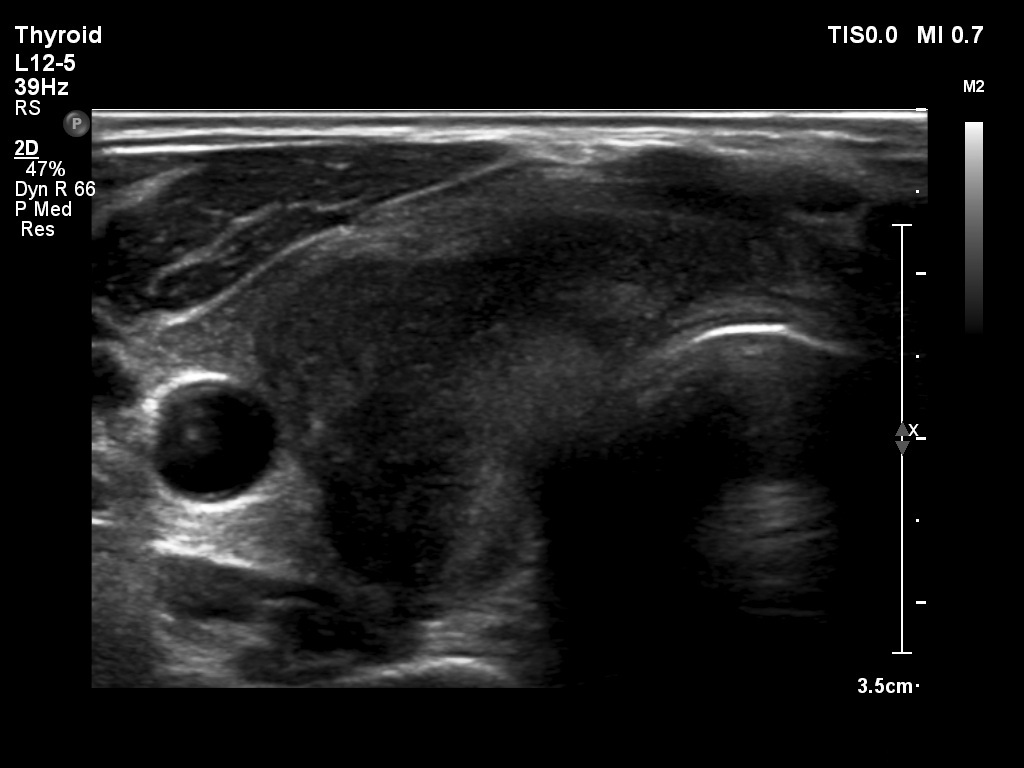

First examination (1st to 3rd rows of images):

Clinical presentation: A 47-year-old man was referred for evaluation of complaints suggesting subacute thyroiditis. He suffered from recurrent attacks of pain in the region of the thyroid radiating to the jaws. The pain was originally located to the left side of the neck but 2 weeks before the visit, both sides of the neck were affected. He had subfebrility, occasionally fever. He got 3 courses of antibiotics without any effect. The GP initiated investigation toward lymphoma of the neck.

Palpation: Both lobes were hard and painful.

Laboratory tests: euthyroidism with TSH-level 0.27 mIU/L, FT4 16.7 pM/L, CRP 35.1 mg/L, ESR 41 mm/H, aTPO 10 U/mL.

Ultrasonography: Both lobes presented hypoechogenic ill-defined areas. The echogenicity index was 80% in the right lobe while 20% in the left thyroid. The vascularization was significantly decreased.